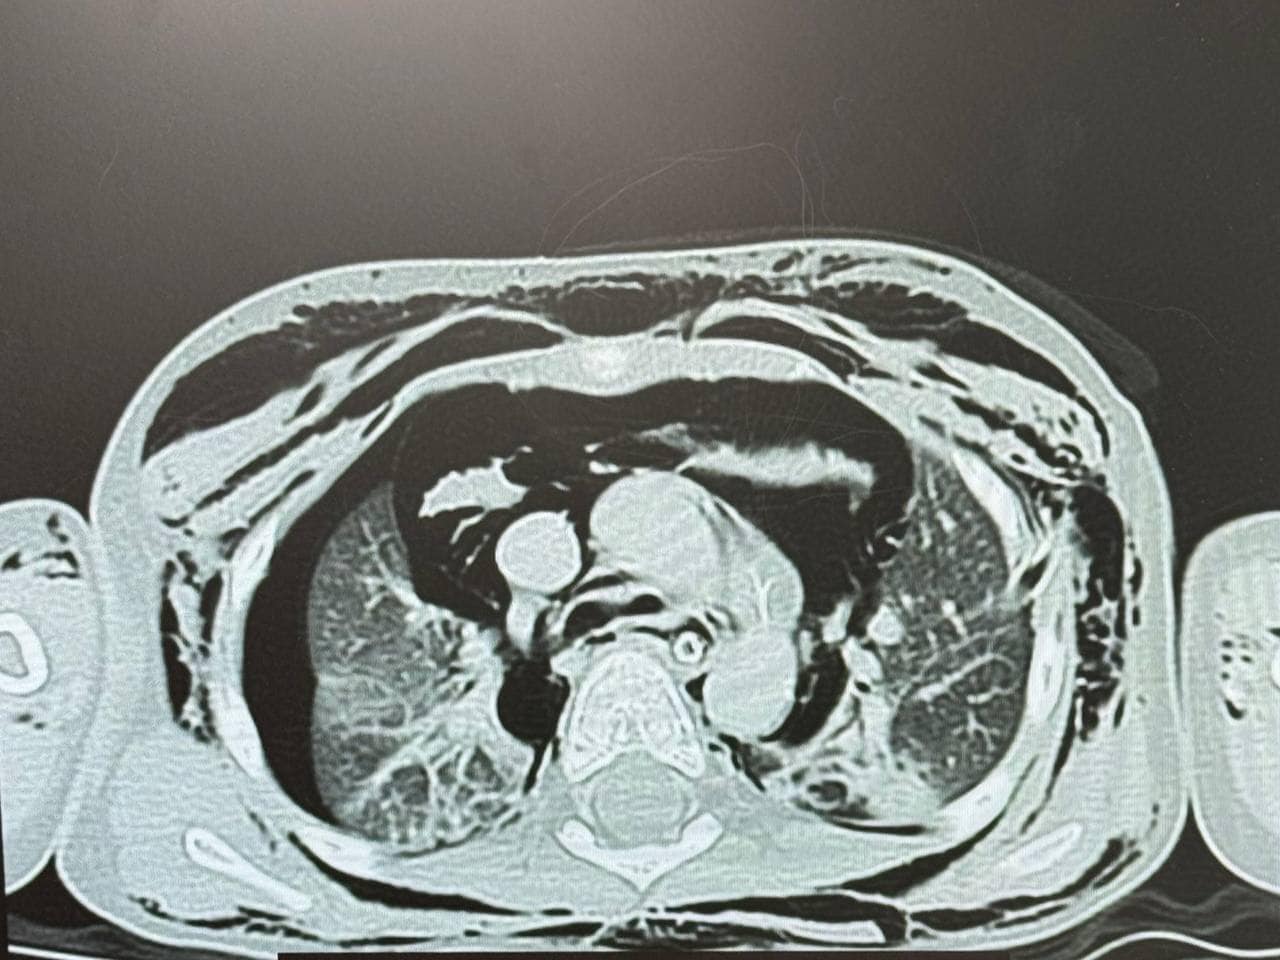

Після проведених рентгенівських обстежень та КТ лікарі виявили накопичення повітря в середостінні, під шкірою голови, шиї, грудної клітки. Це свідчило про порушену цілісність дихальних шляхів у хлопчика. Вже наступного дня Лука був терміново доставлений до «Охматдиту».У медзакладі команда спеціалістів оперативно зібралася для термінового обстеження та визначення плану подальших дій. Під час КТ, рентгенівських обстежень та бронхоскопії у дитини виявили розрив трахеї. Дефект був розташований на задній стінці трахеї, півтора сантиметра нижче голосових зв’язок. Довжина розриву становила 2,5-3 сантиметри.